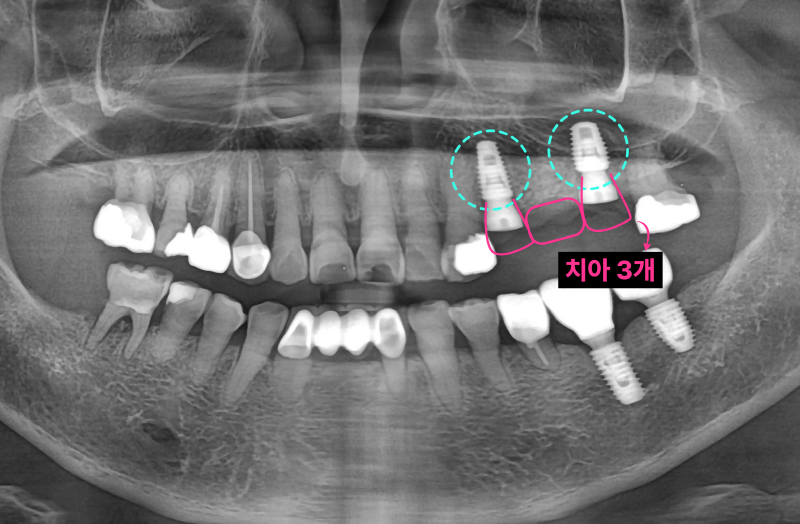

이미 신경치료된 치아 뿌리 끝에 염증이 잡혀있고 브릿지 아래로 2차충치가 크게 생겨서 임플란트로 치료 계획을 정했습니다. 임플란트 2개를 심고 치아 머리(크라운) 3개를 만듭니다. 여러 개의 임플란트를 심을 때 꼭 개수대로 임플란트를 심을 필요는 없습니다. 과거에는 발치, 상악동 수술, 임플란트를 전부 기다리며 나눠서 진행했는데 시간이 너무 오래 걸립니다. 저는 최대한 치아가 없는 기간을 단축시키기 위해서 치아를 뽑고(발치) 동시에 임플란트를 심으며 뼈가 없는 경우 상악동 수술을 동시에 진행합니다.

발치, 상악동 거상, 임플란트 식립 모두 이상적인 모습입니다. 과거 임플란트가 없던 시절에는 브릿지 치료가 일반적이었습니다. 하지만 현재는 치아가 없을 때 양 옆의 치아를 갈아서 씌우는 치료는 임플란트 등장으로 없어지고 있습니다. 또한 오래된 브릿지가 흔들리거나 잇몸에 염증이 생긴다면 임플란트로 교체가 필요할 수 있습니다.